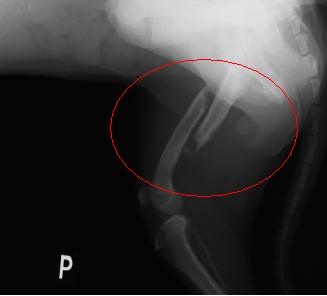

3 mesačné šteniatko malinké, ktoré bojovalo s infekciou netušili sme či Ajša prežije. Našťastie zabojovala no prišlo ďalšie zistenie, ked sa Ajša nedokázala postaviť na nôžku.

Po zložitej operácií už Ajša behá. Poďakovanie patrí všetkým dobrým ľudom, ktorí finančné podporili drahú operáciu nôžky. Ďakujeme za Ajšuľku.